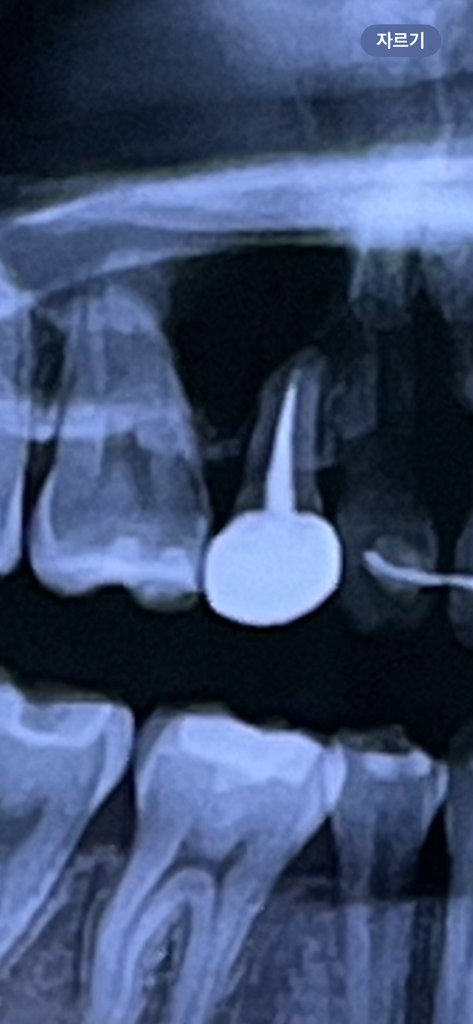

크라운 씌운 곳 염증이 생긴 건가요?

며칠 전에 잇몸치료를 받았긴 했는데 여기가 여전히 누르면 아프더라구요 ㅠ 잇몸 뒤 쪽도 저 치아 주위로 부어있어서 이게 염증인 건가 해서요 ㅜㅜ 잇몸 치료 했는데도 호전이 없으면 어떻게 해야 할까요

신경치료까지 하고 나서 크라운 치료를 한 치아 뿌리끝에 염증이 광범위 하게 잡힌거 같습니다. 저정도라면 대학병원 보존과를 가셔서 상담을 받아보시는게 좋을것같습니다. 재 신경치료, 치근단 절제술을 해서 안되면 발치를 하셔야될수도 있습니다.

사진이 어두워서 잘 안보이지만 염증 가능성은 있어 보입니다. 해당 치아가 문제면 뜯고 치료해야할 수도 있습니다.

파노라마 방사선 사진이고, 신경치료 전/후 비교사진이 없어 애매하긴 하나 현재 사진상으로는 좋지 않아보입니다. 어느정도 치아 뿌리끝 염증이 진행되어 잇몸뼈가 녹은 상태로 보여집니다